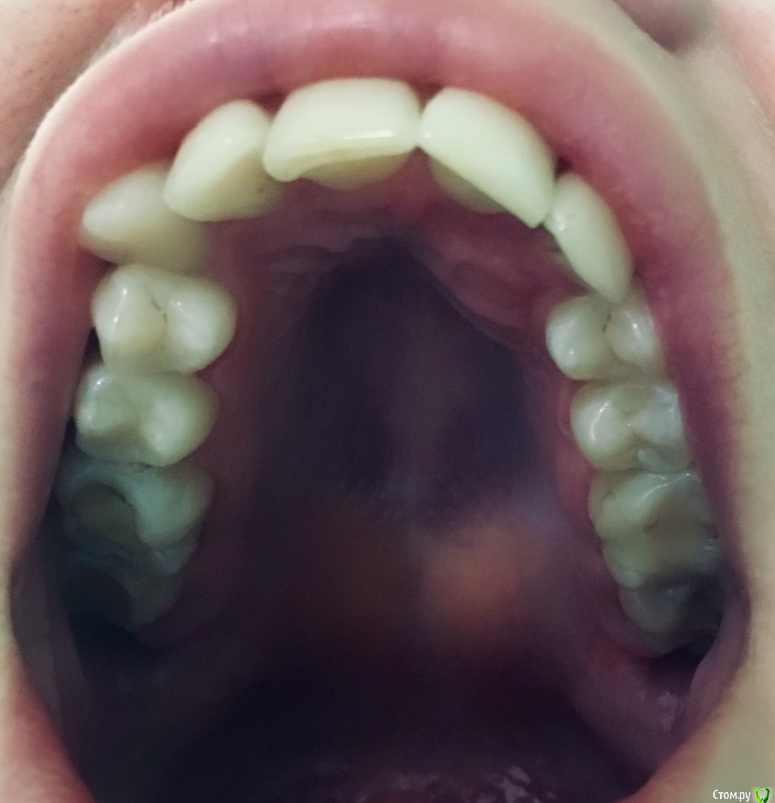

Уважаемые доктора, помогите пожалуйста! В моем городе только один врач-ортодонт, а выехать куда-либо на консультацию с другим специалистом, к сожалению, пока возможности не имею, а ситуация сложная. Суть вопроса такова. У меня есть ретинированный зуб, клык. В детстве я носила брекиты, лечение длилось три года. Тогда клык мне убирать не стали, просто выровняли зубной ряд, в результате на верхней челюсти сместился центр, а нижний ряд выпрямили. Ретейнеры не установили, в результате сейчас такая ситуация (фото). Спустя 15 лет решилась снова заняться решением своей проблемы, так как просто эстетикой это уже не ограничивается. Обратилась к тому же доктору, так как, повторюсь, доктор у нас один и работает с давних пор. Что она предлагает: 1) убрать ретинированный зуб 2) удаление одного зуба с нижней челюсти 3) установка брекит-системы и выравнивание. Прикус у меня глубокий. Дело в том, что при выравнивании зубного ряда сверху смещение центра ещё более усугубится ( я так предполагаю). И при удалении зуба с нижнего ряда тоже получится смещение. Хотелось бы узнать мнение, неужели нет альтернативных вариантов? Очень не хочется в результате получить смещённую челюсть((((. Вот так удалю зуб снизу по рекомендации доктора, а, как говорится, зуб не волос, новый не вырастет. Прошу, помогите пожалуйста(((.

Спасибо Вам огромное, что подсказали, небезразличным людям добро возвращается в стократном размере! А для меня это целая жизнь, с желанием жить ее без комплексов и в здравии)))Прикладываю фото!)